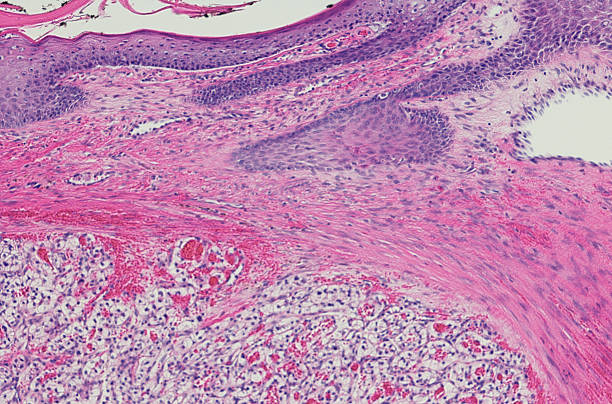

신장암은 흡연, 비만, 고혈압 등과 관련된 원인이 있을 수 있습니다. 그러나 암의 발생 원인을 규명하는 것보다 더 중요한 것은 조기 발견입니다. 신장암은 양쪽 신장에서 동시에 발견되는 경우가 드물며 대부분 한쪽에서 발견됩니다.

신장암이 조기에 발견되면 치료 가능성이 높아집니다. 이러한 조기 진단을 통해 작은 크기의 암이 발견되면 신장을 완전히 제거하지 않고 부분적으로 절제하는 수술이 가능하며, 이는 최근에는 로봇을 이용한 절제술로 더욱 효과적으로 수행됩니다.